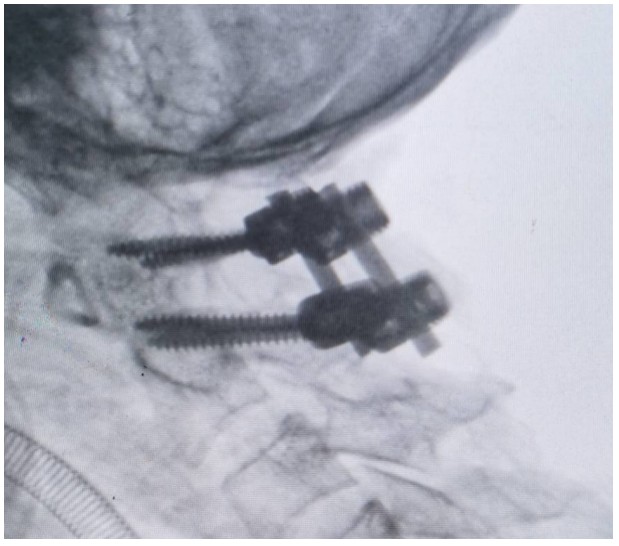

國慶節(jié)前一天,譚女士不幸被門框砸傷頸部,劇烈的疼痛和頸椎的活動受限讓她的世界瞬間陷入了黑暗。在經(jīng)歷了初步的檢查后,譚女士被診斷為寰椎骨折,這個診斷如同一道晴天霹靂,讓她和家人的心沉入了谷底。絕望中,譚女士被緊急轉(zhuǎn)至衡陽市中心醫(yī)院骨科一區(qū)(脊柱外科),錢軍博士及其團隊在接到這一緊急病例后迅速接診,經(jīng)過細(xì)致的病史詢問、體格檢查和影像學(xué)資料分析,確診譚女士的寰椎骨折伴有寰樞椎體不穩(wěn)定,迫切需要手術(shù)治療以恢復(fù)其穩(wěn)定性??紤]到上頸椎手術(shù)的高風(fēng)險性,特別是寰樞椎周圍結(jié)構(gòu)復(fù)雜,緊鄰椎動脈和脊髓,手術(shù)過程中的任何微小失誤都可能導(dǎo)致災(zāi)難性后果,錢軍博士團隊頂著壓力,迎難而上,沒有絲毫猶豫,立即行急診手術(shù),投入到緊張的救治工作中。

術(shù)中,錢軍博士團隊展現(xiàn)出了非凡的勇氣和精湛的醫(yī)術(shù)。他們精心準(zhǔn)備,與手術(shù)室和麻醉科的同仁們緊密協(xié)作,以專業(yè)的技術(shù)和精確的操作,成功完成了這一高難度的手術(shù)。手術(shù)室外,譚女士的家人焦急等待,當(dāng)手術(shù)成功的消息傳來時,譚女士的家人不禁流下了感激的淚水。